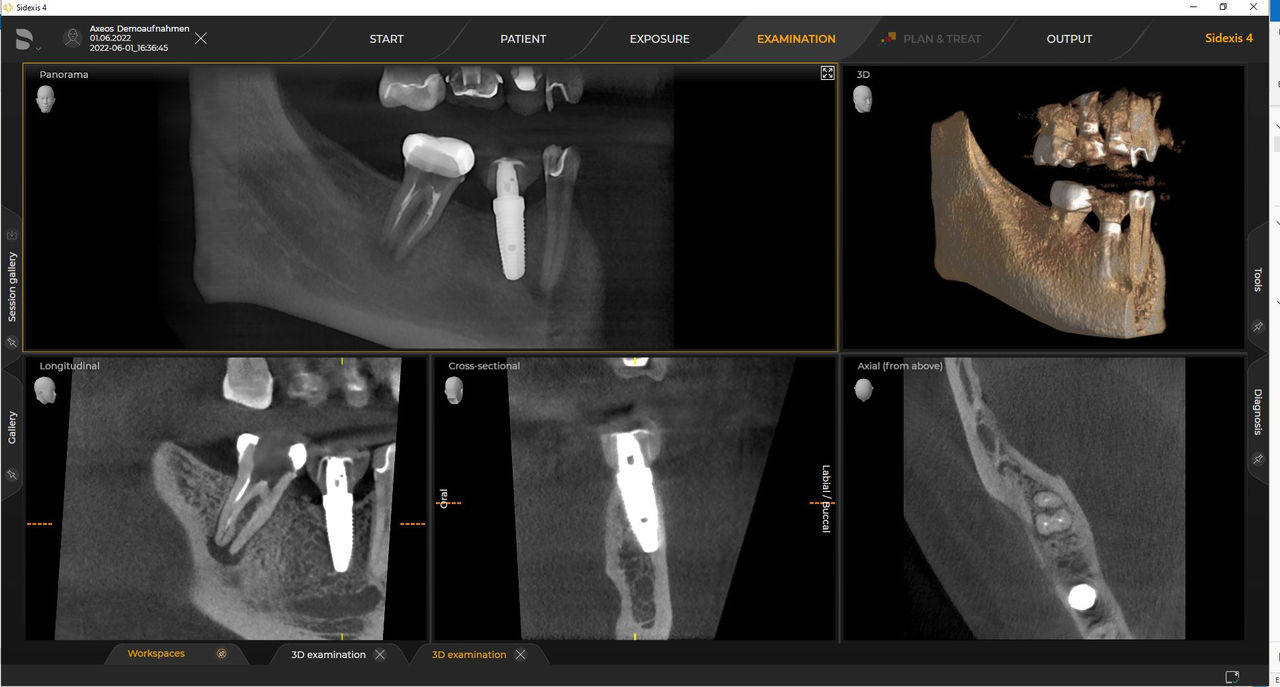

Dank des optimierten Low Dose Modus mit dediziertem Filter wird die Abbildung dichter Strukturen wie etwa Knochen bei stark reduzierter Dosis ermöglicht. Das macht Intelligent Low Dose zu einer attraktiven und effizienten Option bei vielen klinischen Fällen. Ob in der Kieferorthopädie oder Implantologie – mit den Dentsply Sirona Lösungen finden Sie für jeden Fall die optimale Einstellung.

Zahlreiche Volumengrößen sorgen für Flexibilität im Praxisalltag. Untersuchung eines bestimmten Bereichs oder Beurteilung der gesamten Bezahnung einschließlich der Kiefergelenke.

Mit dem Intelligent Low Dose-Modus erhalten Sie 3D-Bilder im Dosisbereich einer 2D-Röntgenaufnahme. Im HD-Modus werden während eines einzelnen Umlaufs bis zu 1.400 Einzelbilder aufgenommen und zu einem 3D-Volumen mit bis zu 80 μm zusammengeführt. Der Vorteil für Sie: rauschärmere Aufnahmen in hoher Auflösung.